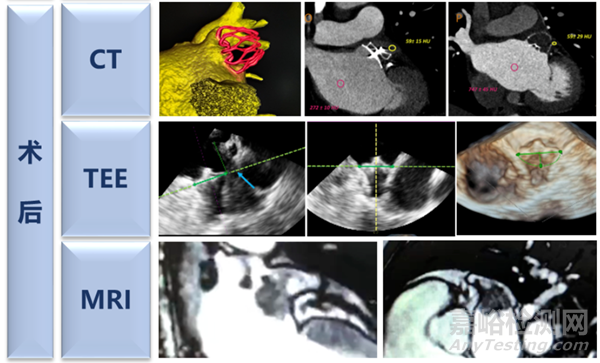

左心耳封堵相關(guān)影像學(xué)技術(shù)發(fā)展演化

左心耳封堵技術(shù)的成熟離不開影像技術(shù)的發(fā)展。WATCHMAN在早期的臨床研究中,均采用的全麻下TEE指導(dǎo)的左心耳封堵術(shù)。近幾年,隨著CT技術(shù)的發(fā)展。其特有的三維建模的優(yōu)勢(shì)以及術(shù)中的影像融合技術(shù)與左心耳封堵的聯(lián)合應(yīng)用越來(lái)越廣泛。無(wú)論是術(shù)前、術(shù)中、術(shù)后,TEE和CT都已經(jīng)成為輔助左心耳封堵開展的利器,確保手術(shù)安全順利的完成。

影像技術(shù)應(yīng)用在左心耳領(lǐng)域的應(yīng)用主要集中在以下幾個(gè)方面:1.幫助術(shù)者熟悉左心耳的解剖結(jié)構(gòu),尤其是心耳內(nèi)部及其毗鄰組織的分布。2. 分析術(shù)前左心耳的多維度測(cè)量結(jié)果,根據(jù)形態(tài)預(yù)判難度及封堵器的選擇。3. 根據(jù)影像探討術(shù)中的封堵策略。精準(zhǔn)操作,注意豬尾、鞘管、封堵器、心耳四者之間的相互關(guān)系。4.并發(fā)癥的監(jiān)測(cè)和評(píng)估,盡量減少并發(fā)癥的發(fā)生。5. 術(shù)后隨訪的評(píng)估,確保患者的最終獲益。